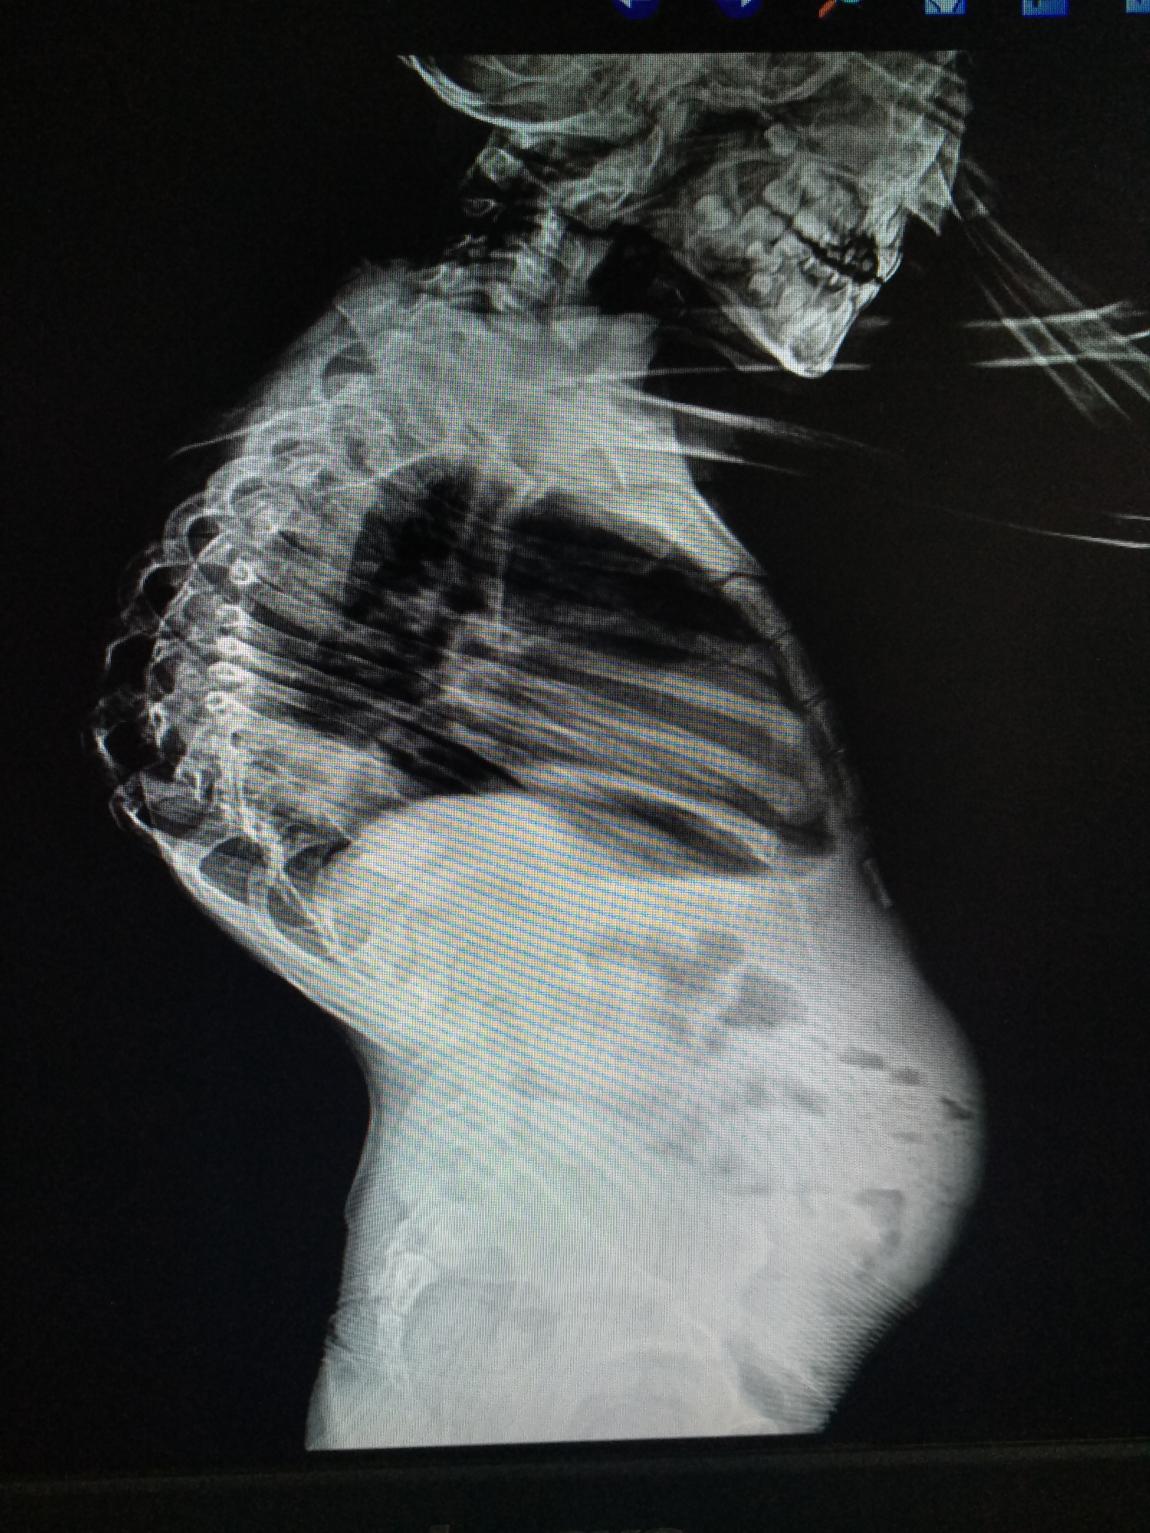

在索县的门诊工作中,田医生遇到一位10岁的藏族姑娘,她从小患有脊柱侧弯,虽然已经11岁了,但身高仅105 cm。严重的脊柱畸形不但对小姑娘的心肺功能造成非常严重的影响,而且给孩子和家长都造成巨大的心理负担。小姑娘家境一贫如洗,加上弟弟也患有下肢疾病,家里的收入仅能支付一家四口吃饭和两孩子上学。田医生在仔细询问病史和详细查体后对小姑娘的病情进行了全面评估,建议小姑娘到北京解放军306医院进行分期矫形手术治疗。田医生向医院领导和索县相关部门的领导汇报了这个病例,306医院的领导已经同意为小姑娘进行手术治疗并减免医疗费用,希望出身贫寒的她可以从此"站立起来"!孩子的母亲得知这一消息后喜极而泣,给解放军306医院的专家们行跪拜礼,用藏语念叨着:*产党共**好!解放军好!

藏族小姑娘患有严重的脊柱侧弯,即将赴京接受一期手术治疗